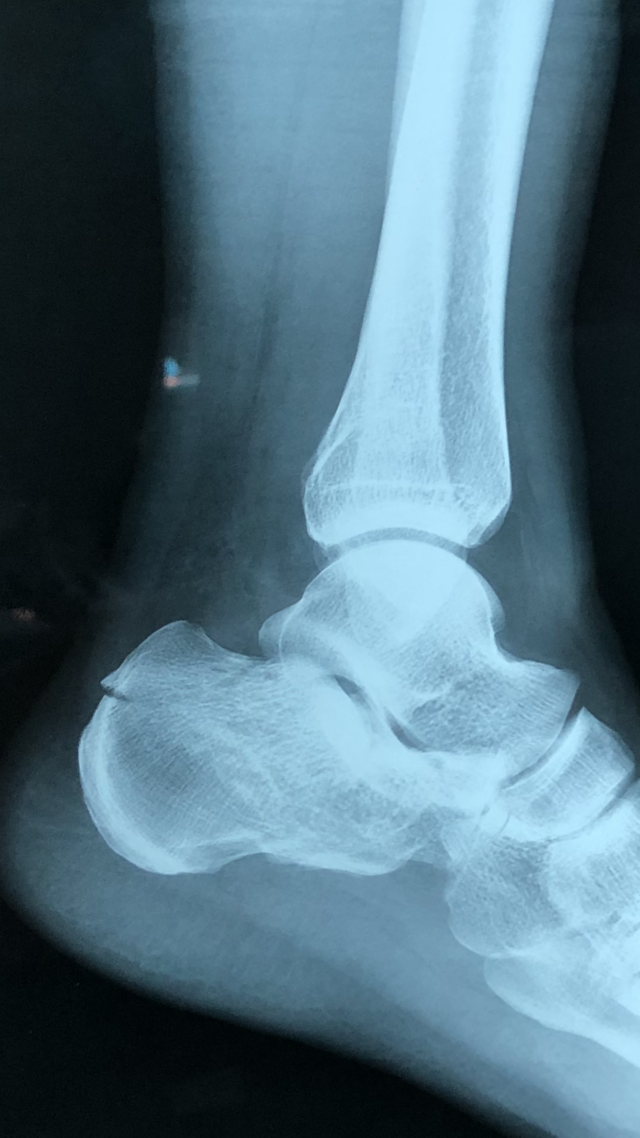

跟骨骨折病例分享 (原创)

640x1137 - 47KB - JPEG